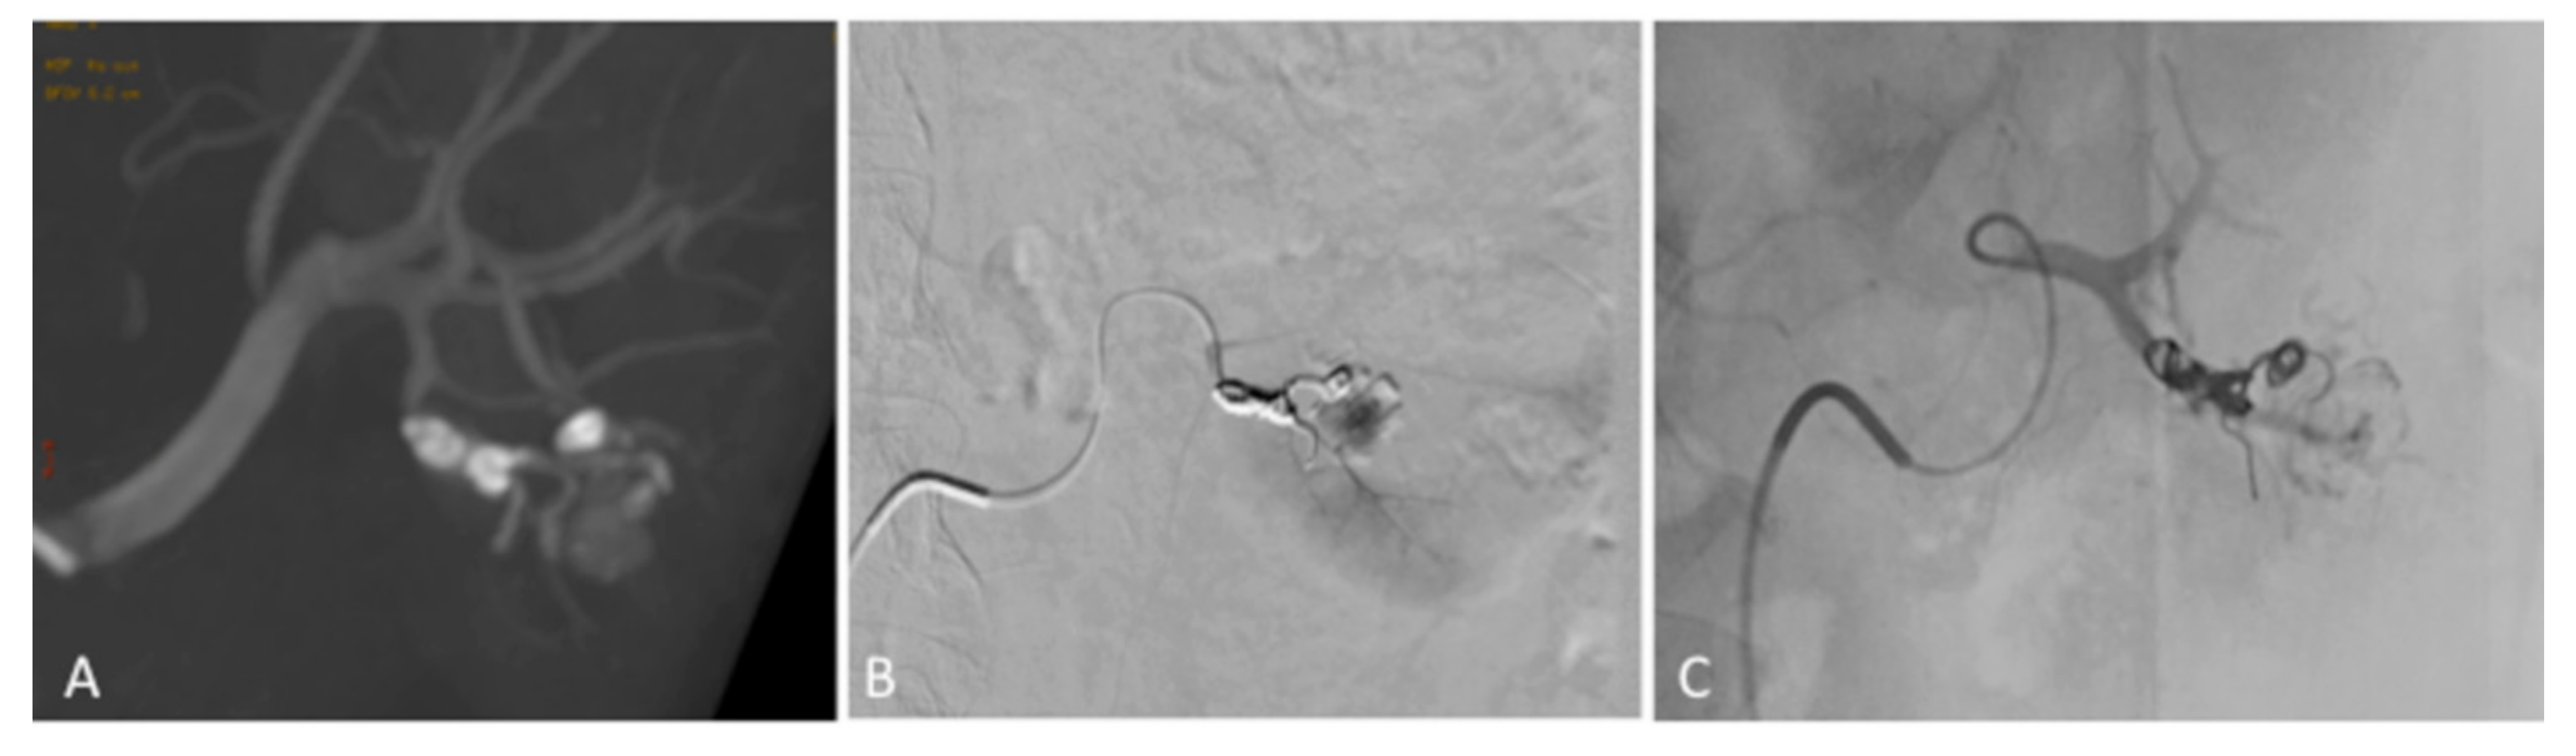

2. Case Presentation